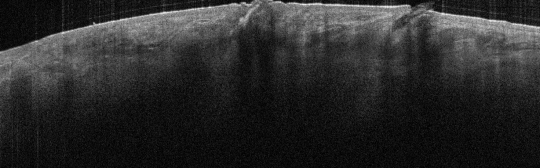

VA38: Upper Forehead, Left of Midline, Actinic Keratosis, Hypertrophic

- Arrows indicate base of epidermal thickening

VA36: Upper Forehead, Left of Midline, Adjacent, Normal